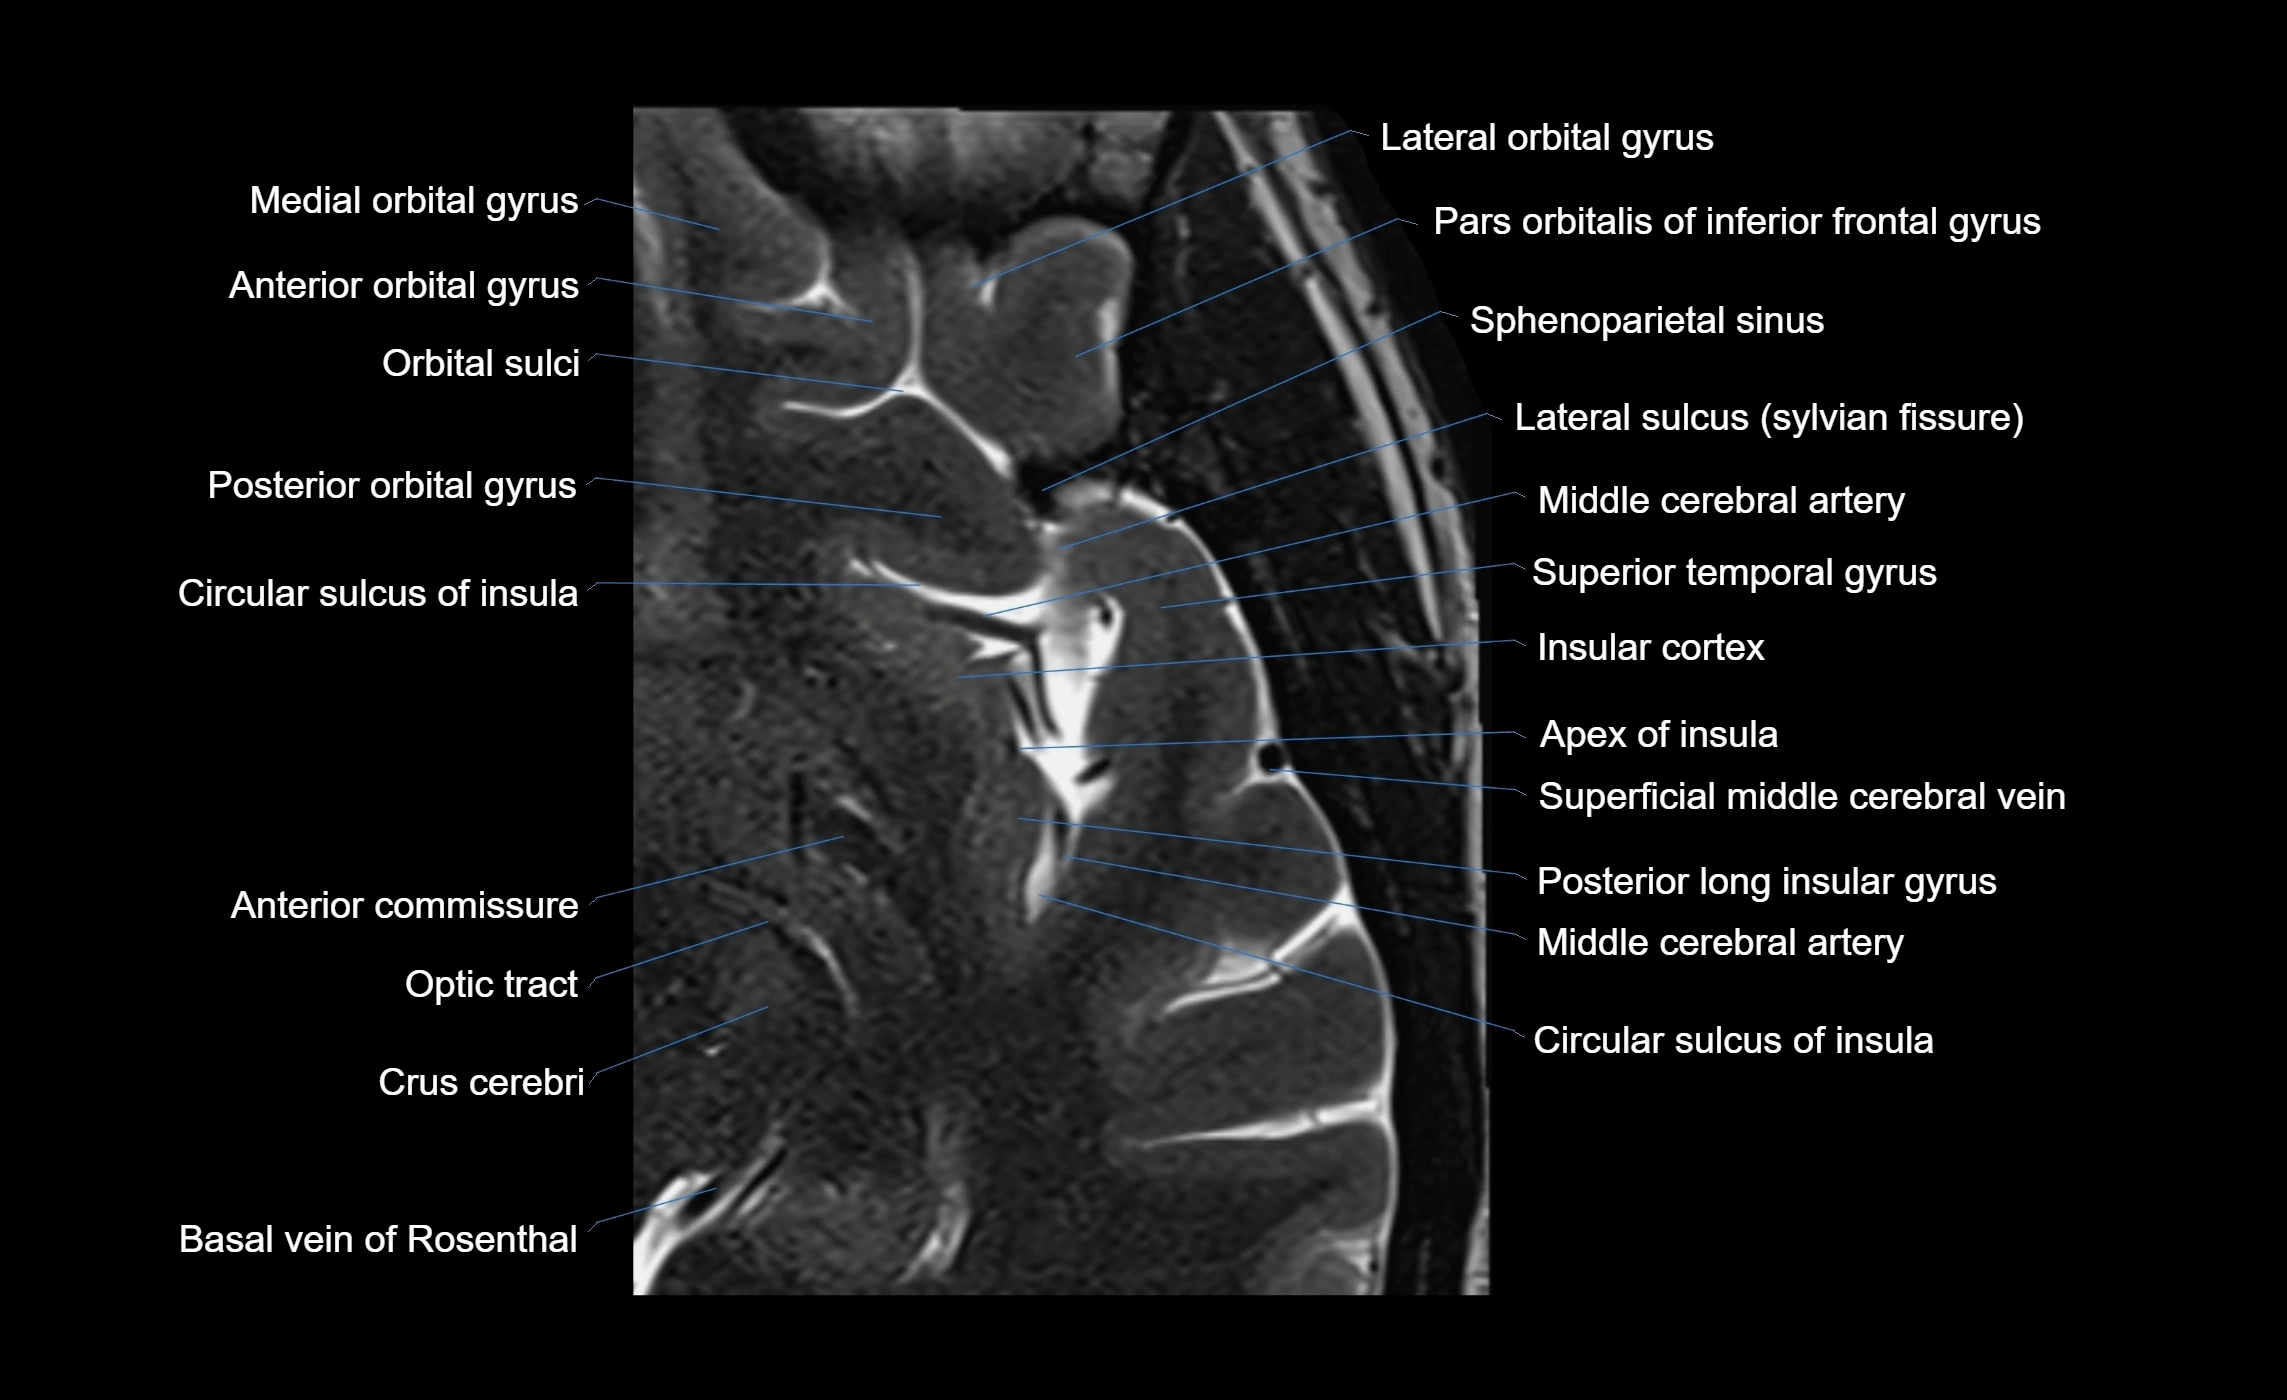

The anterior ascending ramus of the Sylvian fissure is a significant anatomical landmark in the lateral surface of the cerebral hemisphere. It represents one of the key branches of the Sylvian fissure (also known as the lateral sulcus) and plays an essential role in demarcating the boundaries between important cortical regions, notably within the frontal and parietal lobes. Understanding its anatomy and imaging appearance is crucial in neuroradiology, neurosurgery, and neuroanatomy for accurate localization and identification of adjacent brain structures.

• The anterior ascending ramus is a short, superiorly oriented branch that arises from the main stem of the Sylvian fissure.

• It projects upward (anteriorly and slightly dorsally) from the lateral sulcus into the inferior frontal gyrus.

• This ramus separates the pars opercularis (opercular part) from the pars triangularis (triangular part) of the inferior frontal gyrus.

• The anterior ascending ramus marks the boundary between Broca's area and adjacent cortical areas in the dominant hemisphere.

• Supplied predominantly by branches of the middle cerebral artery (MCA), particularly its opercular branches.

• The MCA runs within the Sylvian fissure and provides small cortical branches to adjacent gyri and sulci.

• Drained by superficial Sylvian veins (also called superficial middle cerebral veins), which follow the course of the Sylvian fissure.

• Venous blood ultimately drains into the sphenoparietal sinus and cavernous sinus.

MRI Appearance

• T1-weighted imaging:

• The Sylvian fissure and its anterior ascending ramus appear as low-signal intensity (dark) CSF-filled clefts between the gyri.

• Clear demarcation between adjacent gray and white matter.

• T2-weighted imaging:

• The fissure, including the anterior ascending ramus, is hyperintense (bright) due to CSF signal.

• Better visualization of the separation between opercular and triangular parts of the inferior frontal gyrus.